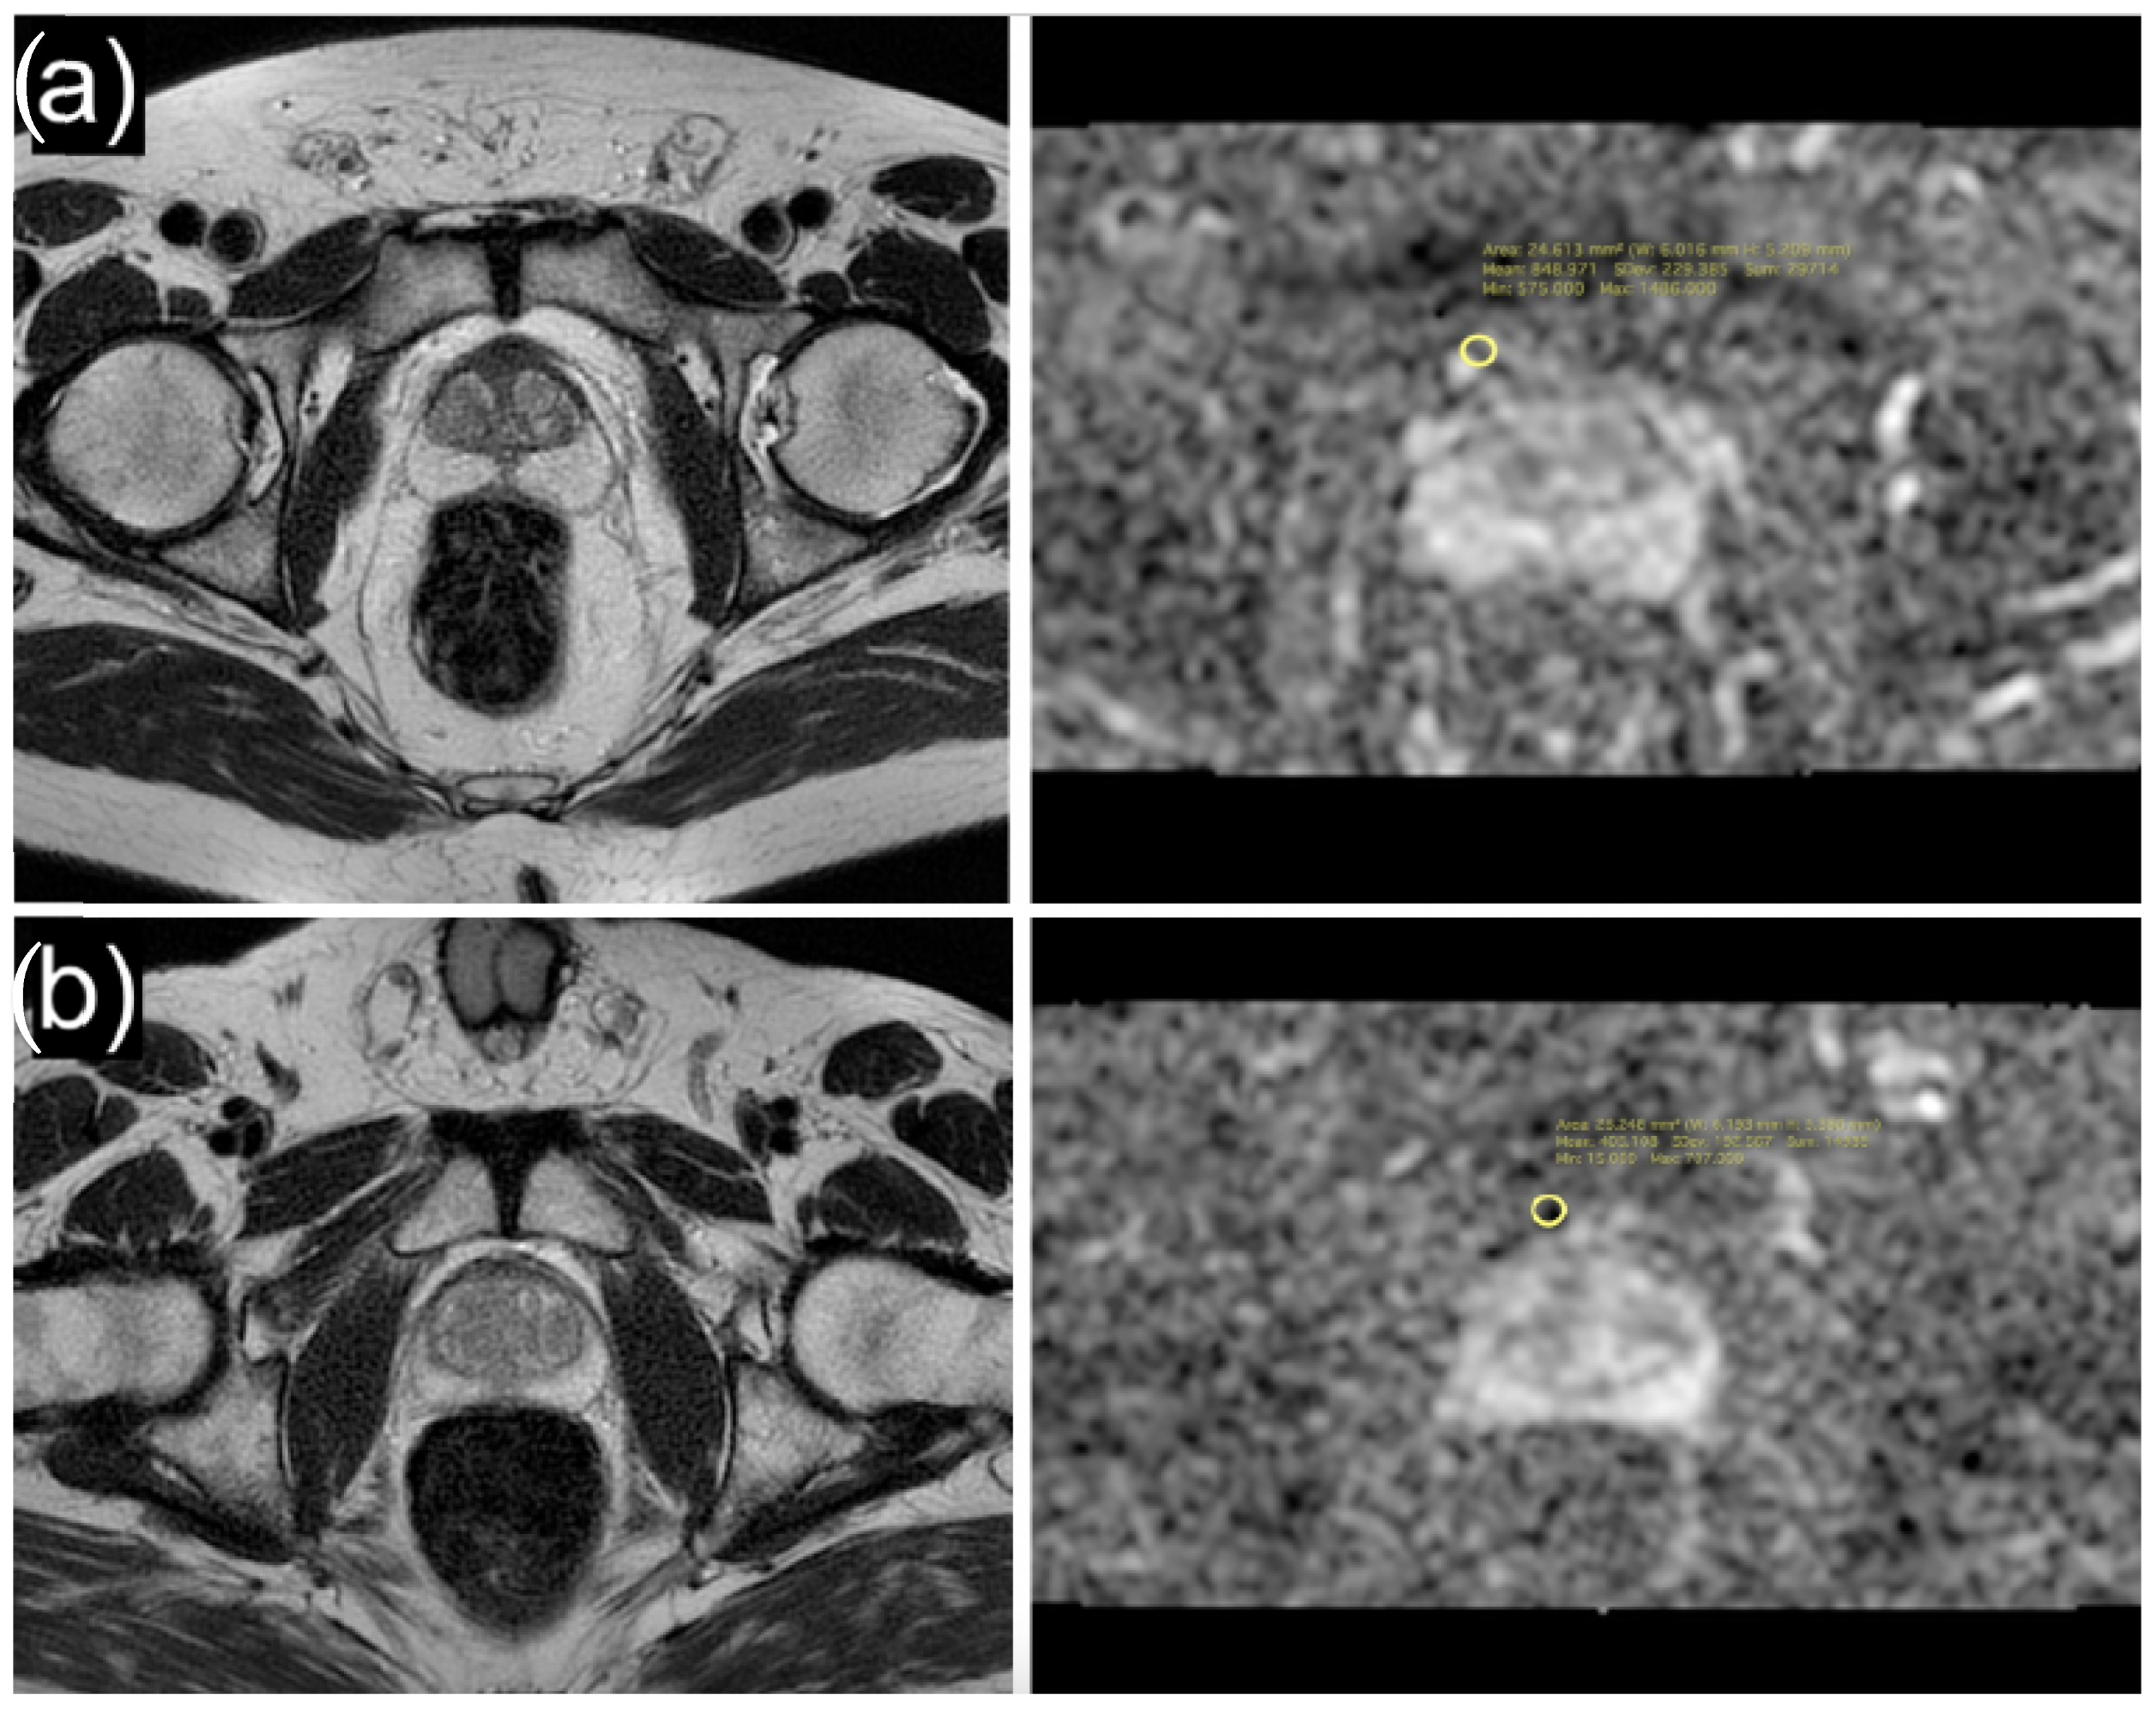

2.2. MRI Acquisition

| Periprostatic adipose tissue ADC | 876 (654, 1112) | 1003 (773, 1299) | 972 (559, 1103) | 656 (455, 952) | <0.001 |